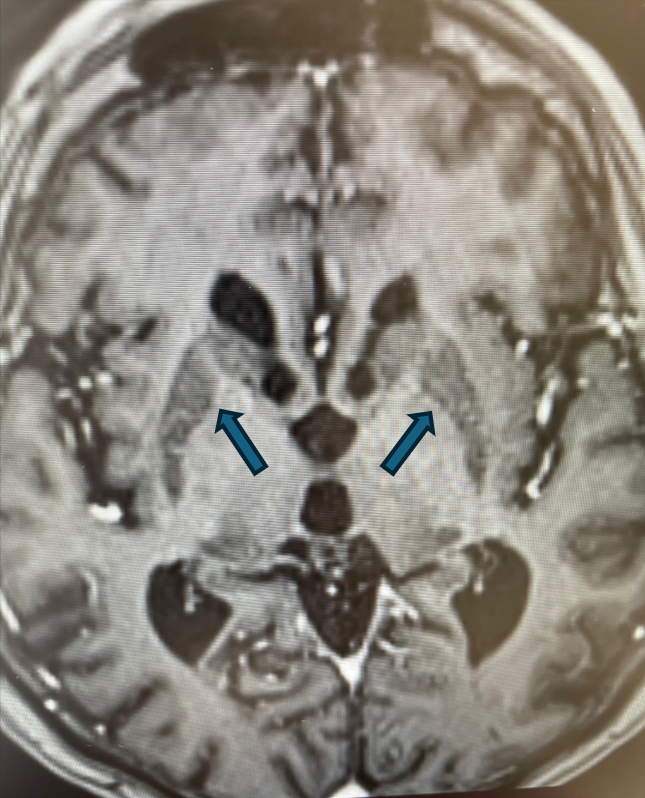

Rycina 3. Cechy akumulacji jonów żelaza w obrębie jąder czerwiennych. (T1).

rycinka